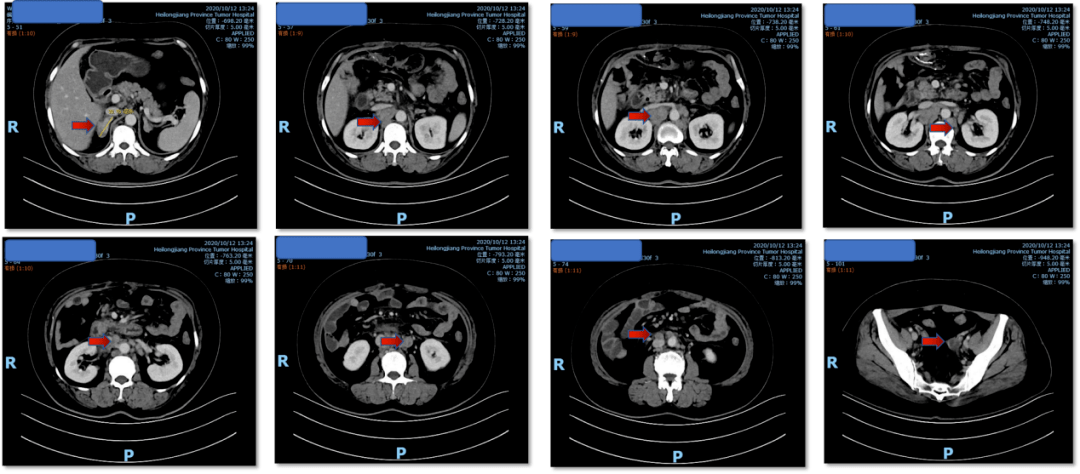

其它 外一18床 韩凤军 直肠癌病情汇报 写美篇腹部强化ct动脉期表现